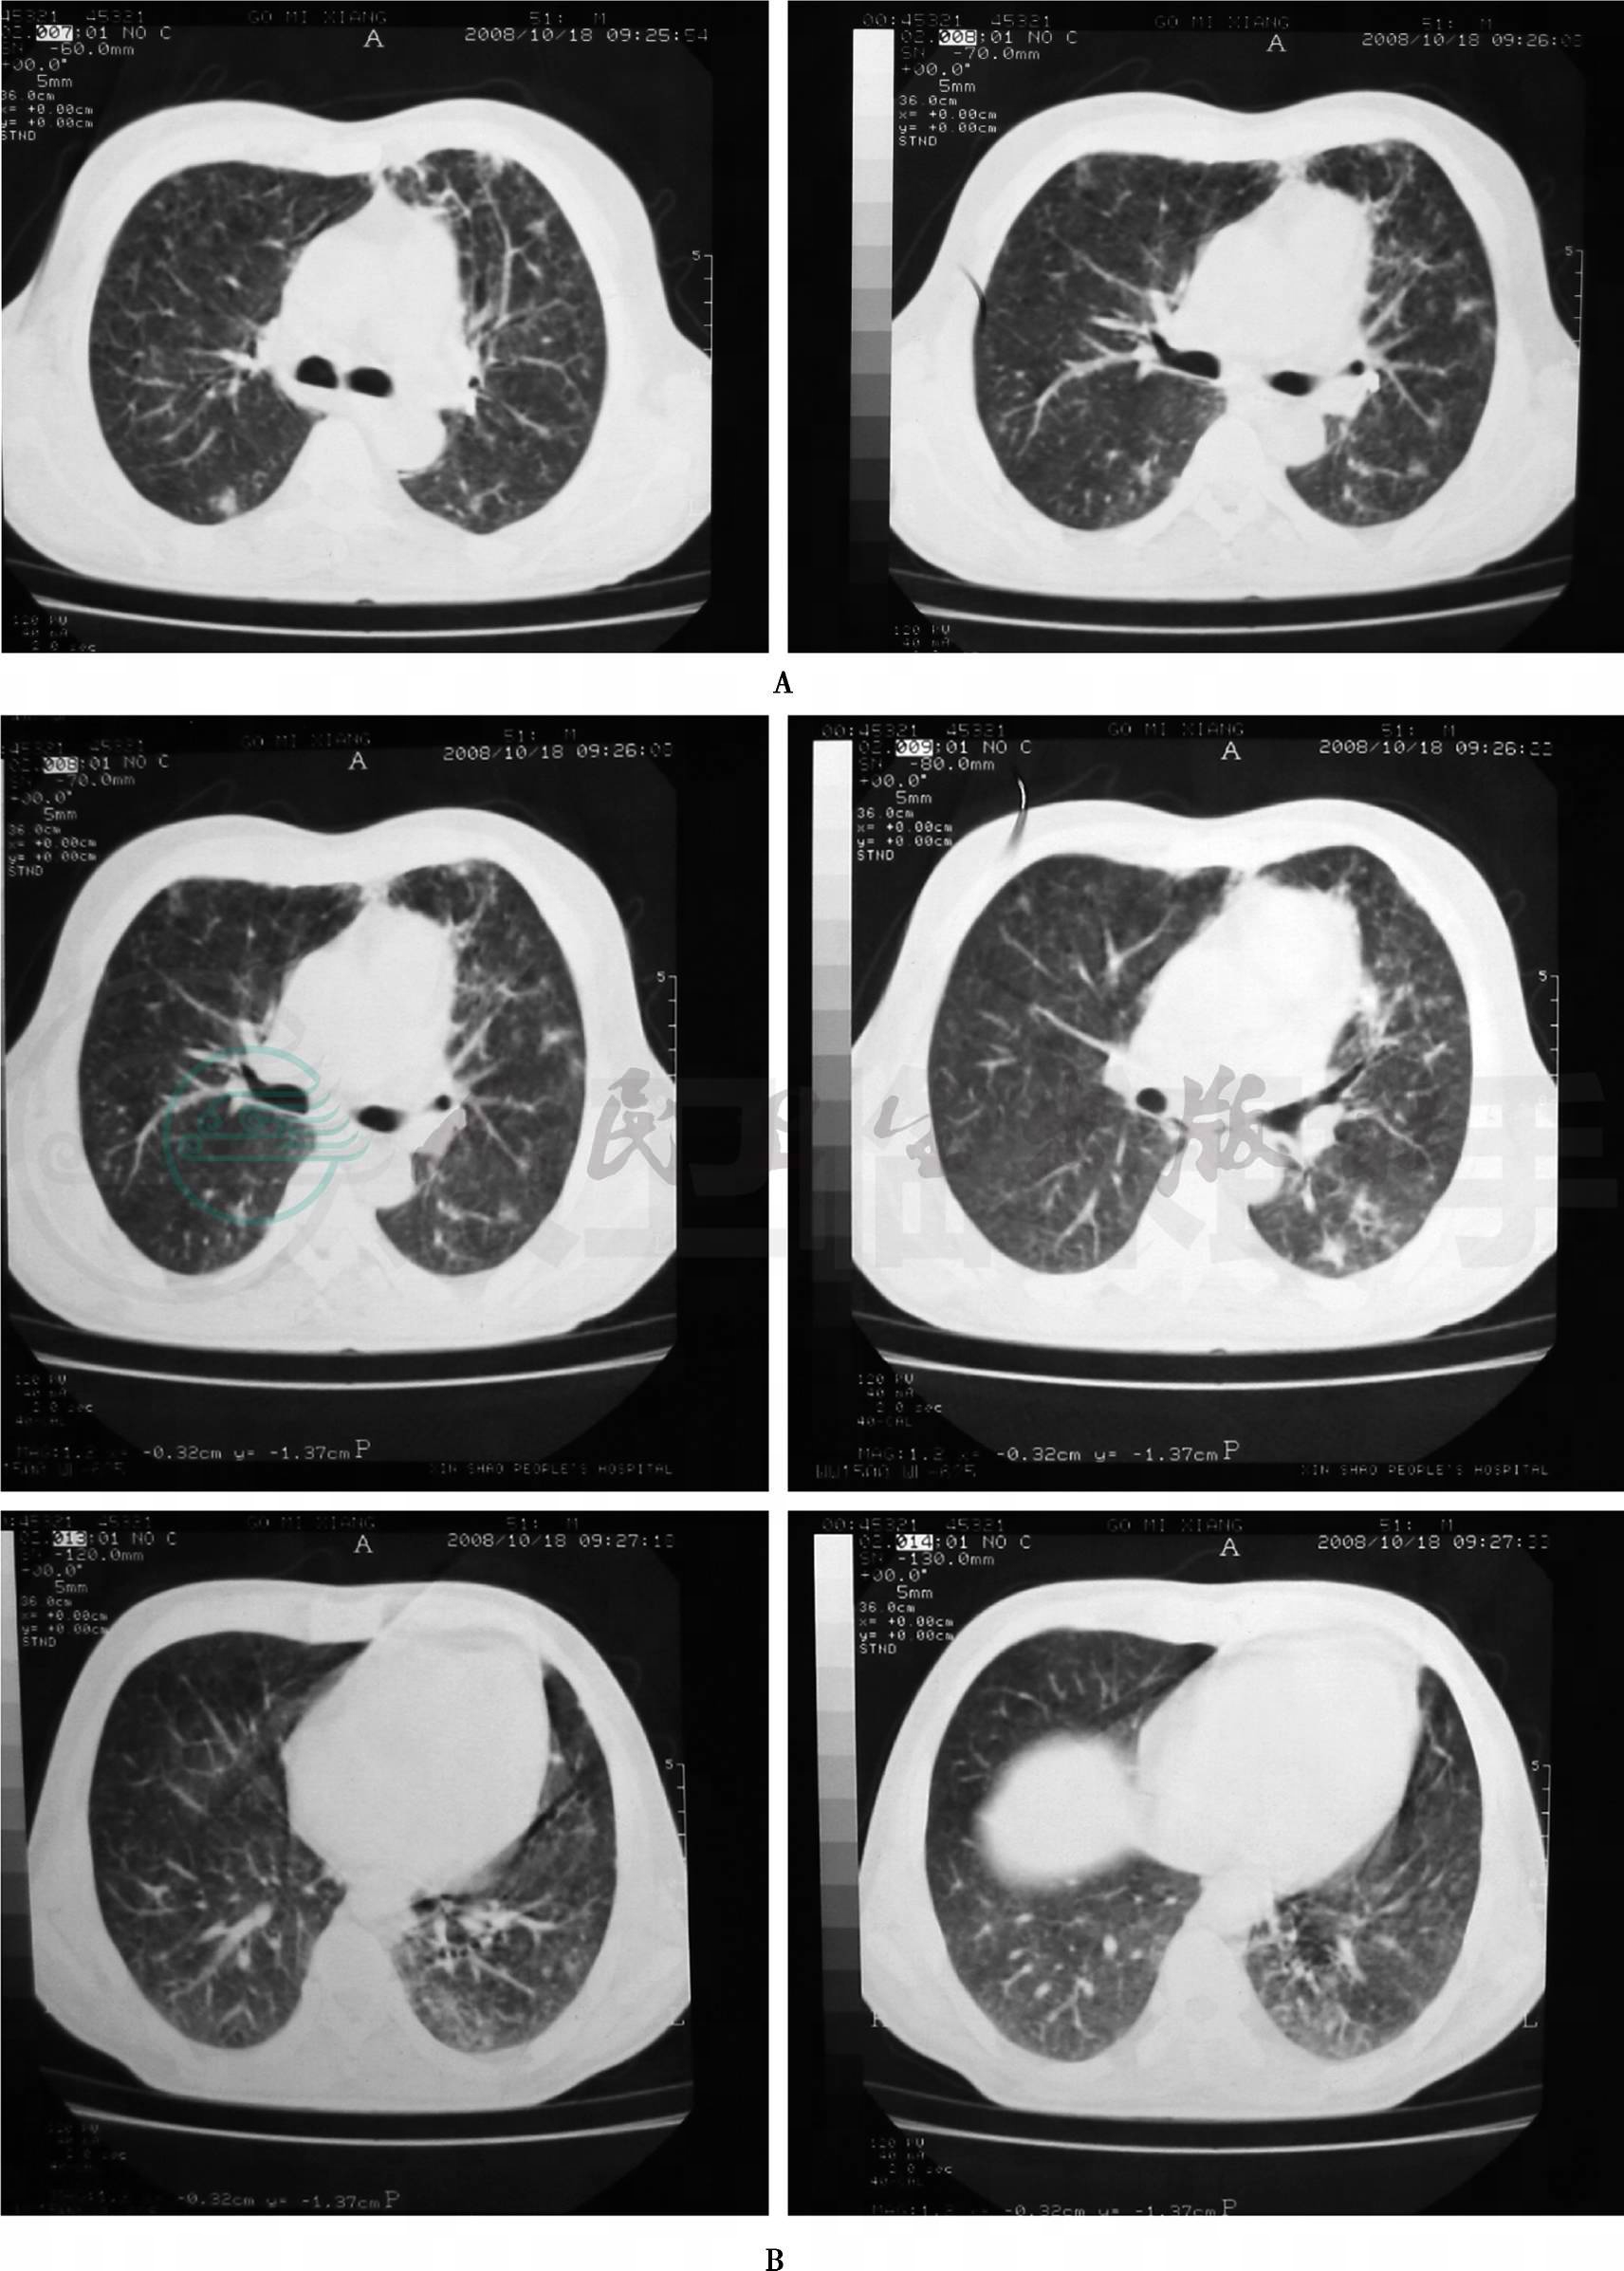

患者,男性,51岁,因反复发热、咳嗽、气促半年,加重1个月于2009年3月25日入院。患者于2008年9月26日无明显诱因而出现发热,最高体温达41℃,伴胸闷、气促,偶有轻度咳嗽,咳少量白色黏液痰,不伴畏寒、寒战、咯血、痰中带血、胸痛、头晕等症状,在当地医院住院治疗,查肺部X线片示双肺渗出病灶,予“头孢哌酮/舒巴坦、加替沙星”抗感染,体温曾一度降至正常后再次升高;10月6日肺部CT(图1)示双上肺及左下叶病变,考虑肺结核可能,遂予“异烟肼、利福平、乙胺丁醇、吡嗪酰胺”抗结核治疗,1周后出现发热、全身皮疹,改为“利福喷丁胶囊、对氨基水杨酸、异烟肼片”,无明显不适,体温正常出院。

图1 肺CT(2008-10-06)